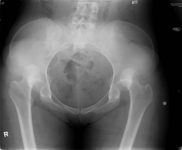

Joint dislocation

X-ray showing bilateral hip posterior dislocation